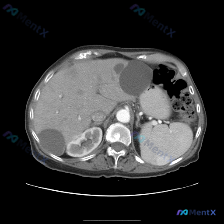

这是一张上腹部增强CT横断面(软组织窗),对比剂显影良好,主要观察到两个核心异常:

- 肝脏:肝左外叶、右后叶各见一个类圆形低密度灶,边界清、无强化,符合典型肝囊肿表现;

- 脾脏:脾实质内见一个类圆形、边界尚清、稍高密度/等密度结节;

- 其他:腹膜后无肿大淋巴结,无腹水,腹主动脉、双肾未见明确异常。